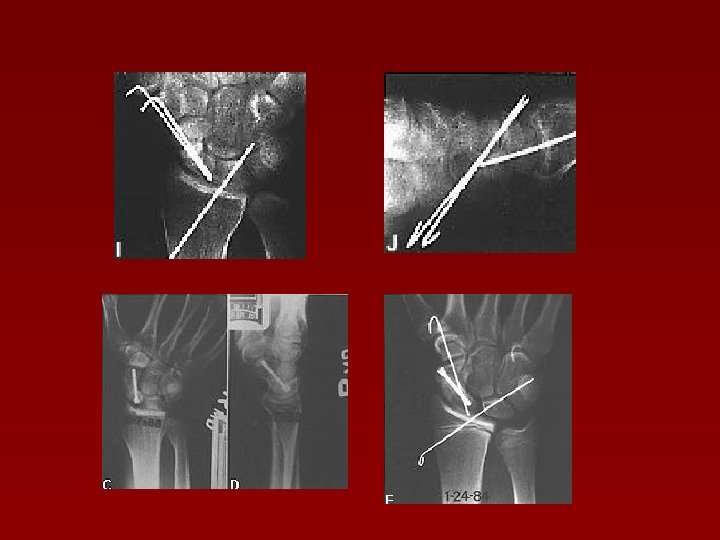

Fractura Bennett Aspect Rtg şi tratament